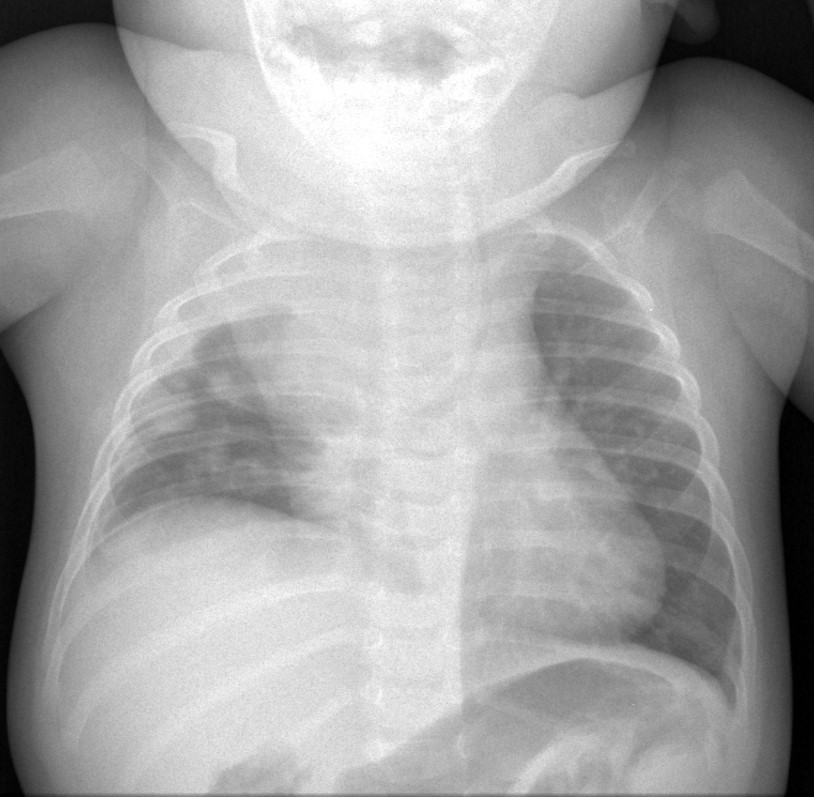

Tumor rabdoide mediastínico con metástasis pulmonares y derrame pleural.

Cuando se sospeche una tumoración torácica, se deberá completar el estudio por imagen mediante ecografía, tomografía computarizada o resonancia magnética

Las masas pulmonares suelen ser lesiones congénitas o inflamatorias. Las neoplasias pulmonares son más frecuentemente metastásicas que primarias.

Las tumoraciones pleurales y de la pared torácica son raras en niños. La mayoría de los bultos asintomáticos en la pared torácica se deben a variantes anatómicas benignas.